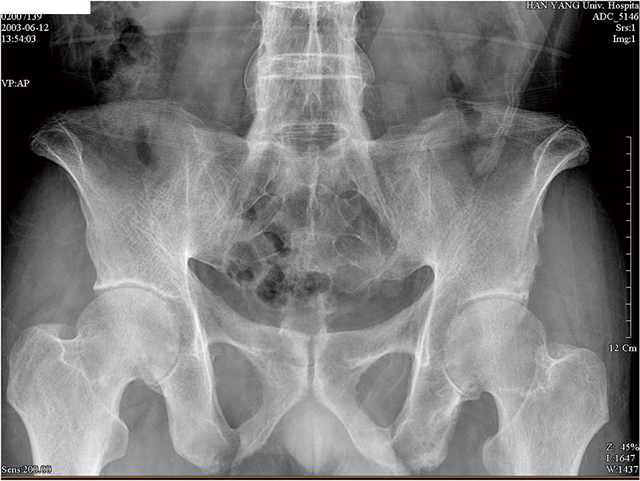

정상인의 골반 엑스레이.

강직척추염 환자의 골반 엑스레이.